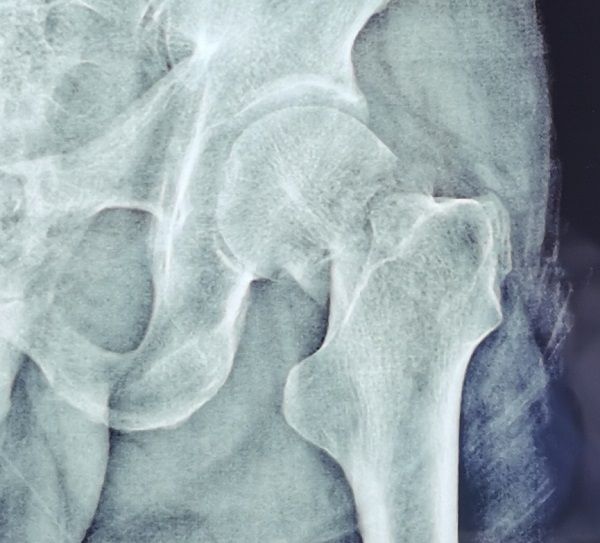

49岁的段先生在工地干活时不幸摔伤,被工友紧急送来咸阳骨科医院创伤骨科就诊。急诊拍片显示左侧股骨颈头下型、GardenⅣ型骨折。造成该类型骨折的暴力大,骨折移位严重,骨折周围血液循环受损严重,骨折不稳定,治疗效果差。伤后影像学检查结果如下:

术前X线片: